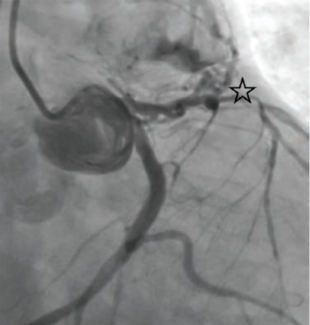

Hanif and Sheikh describe treatment of a sinus of Valsalva aneurysm (SVA), a rare cardiac anomaly characterized by abnormal dilation of the aortic root between the valve annulus and the sinotubular junction, occurring at the level of the...

Coronary artery fistulas (CAF) are rare anomalies with variable presentations and complications including congestive heart failure, myocardial infarction, and arrhythmia depending on anatomy. Congenital etiologies account for the majority of...